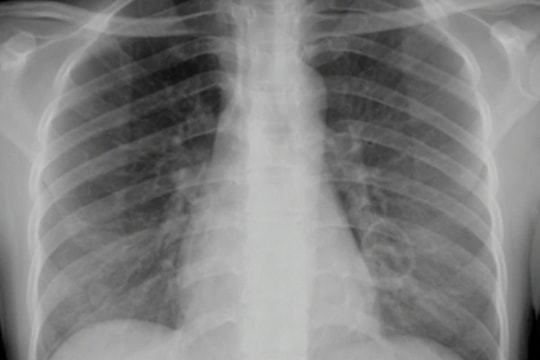

GĐXH – Theo các bác sĩ, người bệnh mắc Whitmore có biểu hiện lâm sàng rất đa dạng, khó chẩn đoán và tỷ lệ tử vong cao ở những trường hợp viêm phổi nặng, nhiễm trùng huyết và sốc nhiễm trùng.

PLBĐ - Thời gian qua, Bệnh viện Nhi Trung ương đã tiếp nhận và điều trị cho 3 ca mắc bệnh Whitmore do vi khuẩn Burkholderia pseudomallei gây ra. Trong đó, có 1 trường hợp đã tử vong trong tình trạng suy đa tạng, hoại tử ruột.

Ngay sau khi tin tức về nữ sinh 9 tuổi nhập viện với triệu chứng sốt cao, tuyến mang tai hai bên sưng to, góc hàm hóa mủ, các bác sĩ đã chẩn đoán mắc bệnh Whitmore - hay còn gọi là "virus ăn thịt người". Vậy căn bệnh này có nguy hiểm không? Nguyên nhân nào khiến căn bệnh này có nguy cơ tử vong cao?